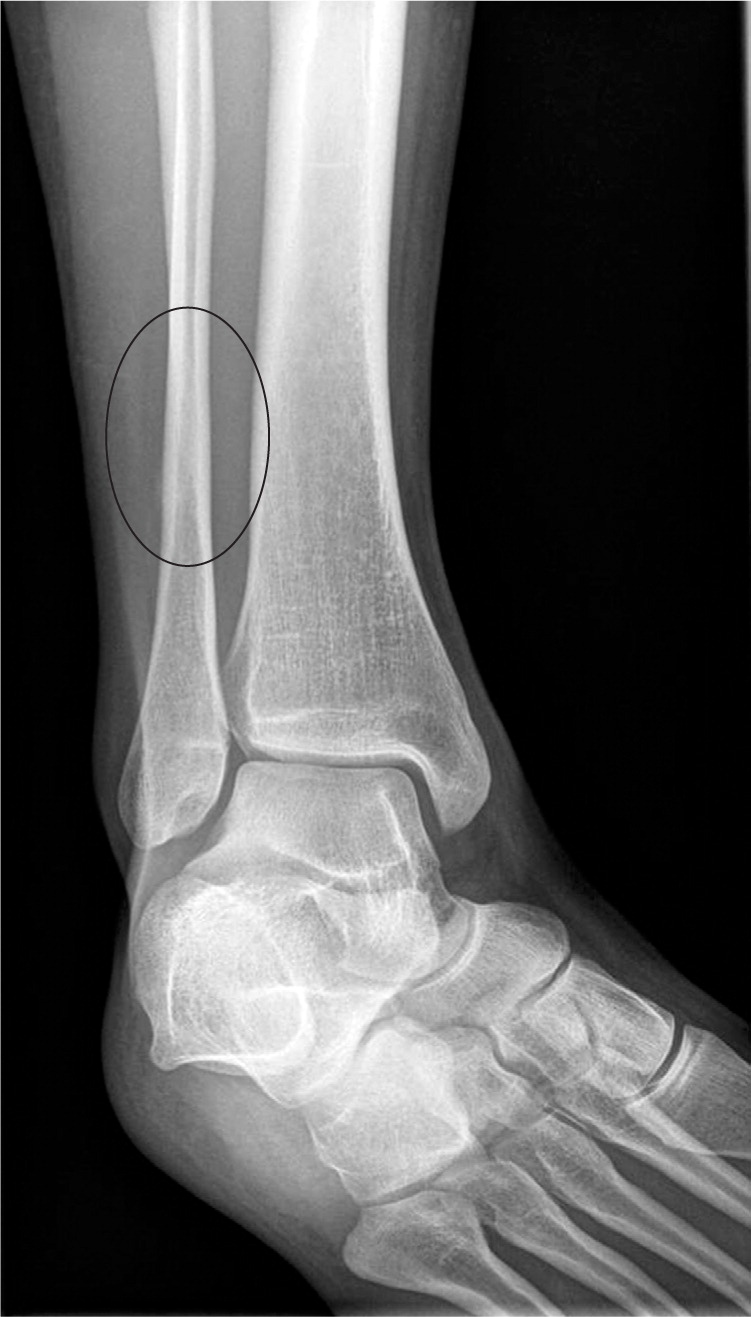

Tibial Stress Fractures in Athletes Orthopedic Clinics Stress Fracture Time To Heal learn about the causes, symptoms, and treatment of stress fractures in the foot and ankle, which are small cracks or bruises in the bones caused by overuse. Learn how to prevent and. some stress fractures don't heal properly, which can cause chronic problems. Many stress fractures of the foot or ankle will heel in 4 to 6 weeks.. Stress Fracture Time To Heal.